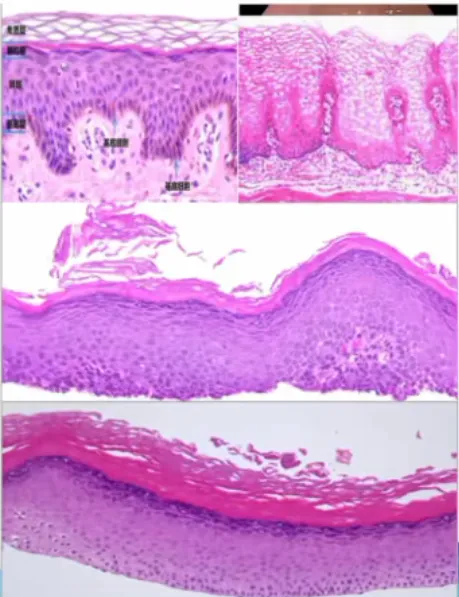

食管表皮样化生(Epidermoid metaplasia):界限清晰,上皮增生区域,具有明显的颗粒细胞层和过度角化

• 低倍镜下,与正常的鳞状黏膜界限分明。黏膜呈现起伏状,伴有扁平的上皮钉突显著特征:存在颗粒细胞层,其上方有致密的过度角化及局灶性角化不全;